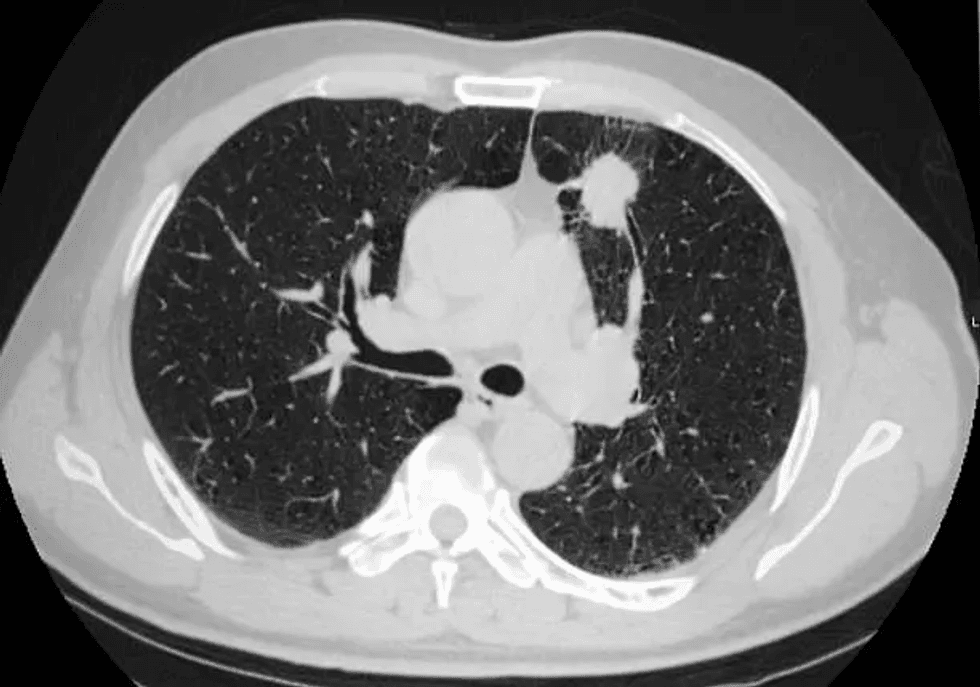

Zbulimi i hershëm me CT me dozë të ulët rrit ndjeshëm mbijetesën nga kanceri i mushkërive, sidomos te duhanxhinjtë. Rekomandimet e ACS theksojnë skriningun vjetor si hap vendimtar për parandalim dhe trajtim në kohë

Pse është kaq i rëndësishëm skriningu?

Kanceri i mushkërive mbetet shkaku kryesor i vdekjeve nga kanceri në SHBA dhe në shumë vende të tjera evropiane. Kur zbulohet në stad të hershëm nëpërmjet CT-së me dozë të ulët, shanset e mbijetesës pesëvjeçare mund të rriten ndjeshëm – deri në mbi 60%, krahasuar me vetëm 20% kur diagnostikohet vonë.

Skaneri LDCT është i shpejtë (zgjat vetëm disa minuta), pa dhimbje dhe ekspozon pacientin ndaj një sasie shumë të ulët rrezatimi. Ai mund të kryhet në shumicën e qendrave diagnostikuese dhe spitaleve.